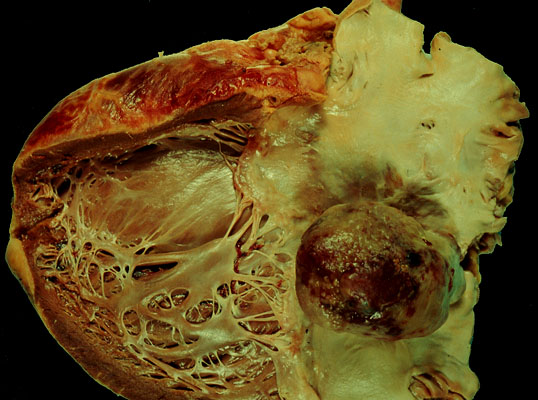

Myxoma, gross

Myxoma of the left atrium. The ball like tumor is attached to the atrial endocardium.